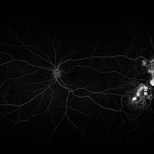

Sickle SC Sea-Fan Neovascularization

52-year-old female with undiagnosed sickle cell, presenting with sickle SC sea-fan neovascularization. FA at 00:55 seconds of the left eye. Right eye presents as well.

Condition/keywords: sickle cell retinopathy